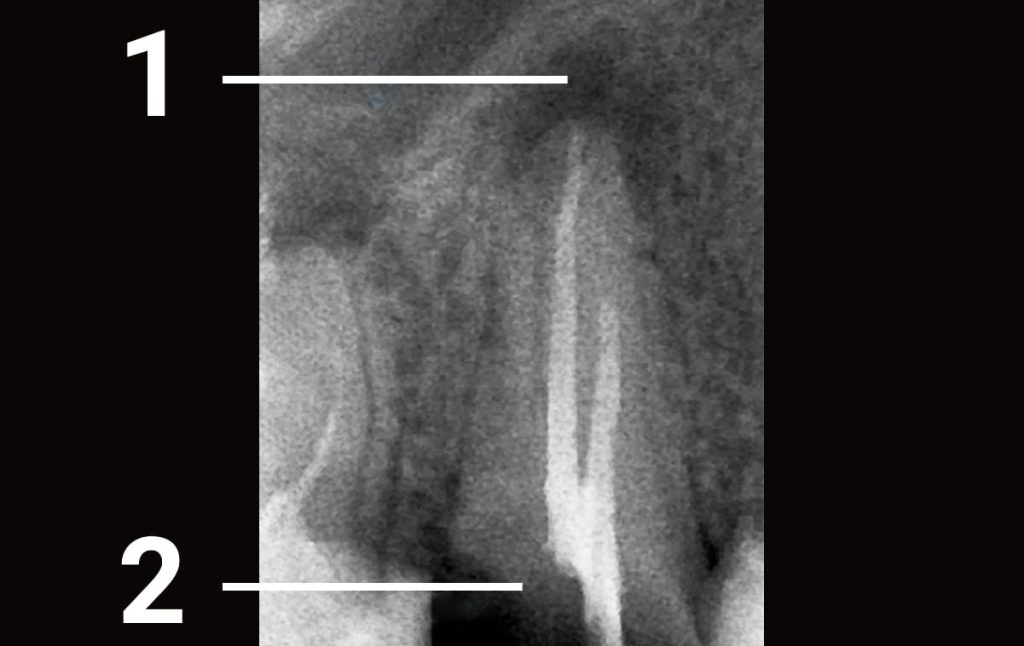

1. The patient contacted the clinic due to tooth decay, which was previously treated in another clinic. Some damaged bone tissue was discovered on the top of the root canal. 1 - bone tissue was damaged due to an incomplete treatment of the root canal 2 - crown of the tooth is damaged